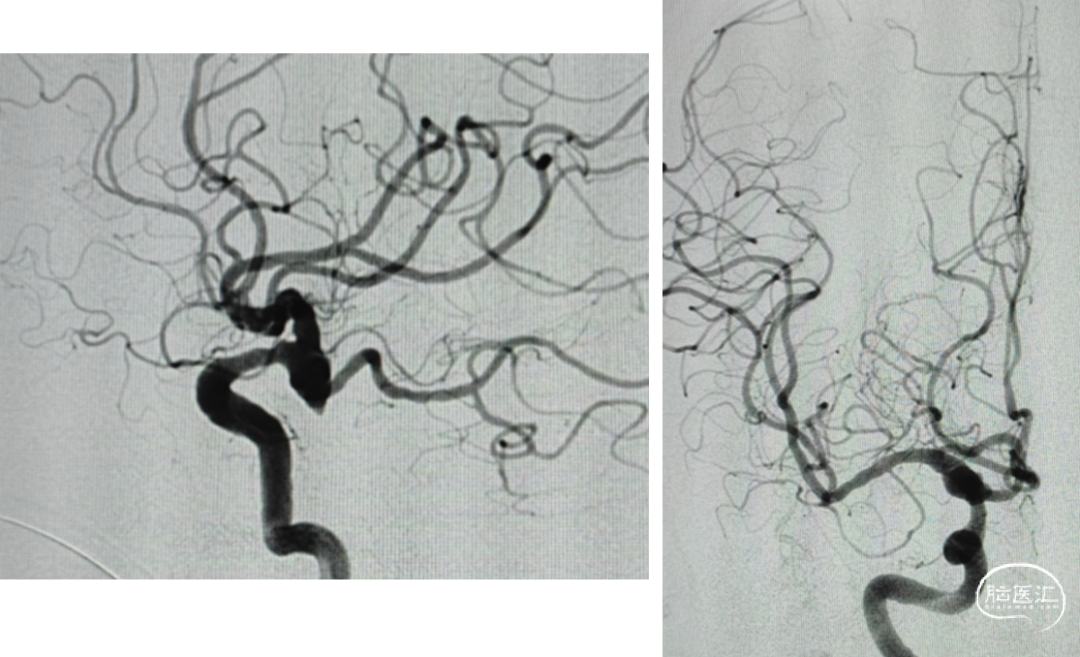

DSA:后交通动脉瘤